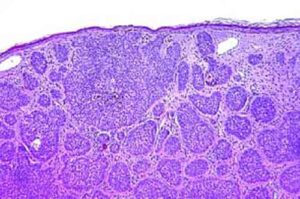

In genere il carcinoma si asporta in ambulatorio. Ora c’è una nuova cura per i pochi pazienti che ne restano...